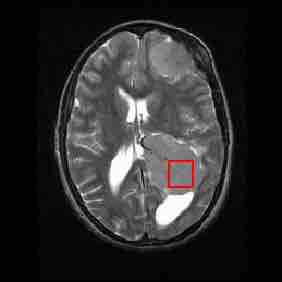

Brain MRI

MRI brain scan (in the axial plane—that is, slicing from front-to-back and side-to-side through the head) showing a brain tumor at the bottom right.